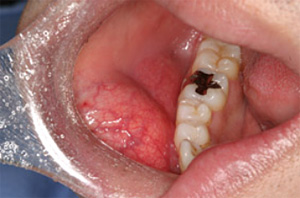

5,智歯周囲炎;智歯、いわいる親知らずの周りの歯肉の腫れのことです。親知らずは大体20歳前後で萌出してくることが多いです。その場合、噛み合わせや咬合は確立しています。なので、スペースが無い場合が多く、その場合横向きや斜め向きなど、曲がって萌出してきます。その為、歯と歯肉の間に隙間が出来てしまう事が多いです。そこに、細菌が溜まることで歯肉が腫れてきます。智歯周囲炎の場合、痛みの度合いはそれぞれですが、ひどい場合は首のリンパまで腫れてくることがあります。軽度の場合は、ブラッシングをしっかりすれば、治ってきますがリンパまで腫れてしまうと抗生物質を服用しなければ治りません。さらに、ひどい場合は点滴などの処置も必要となってくる場合があります。